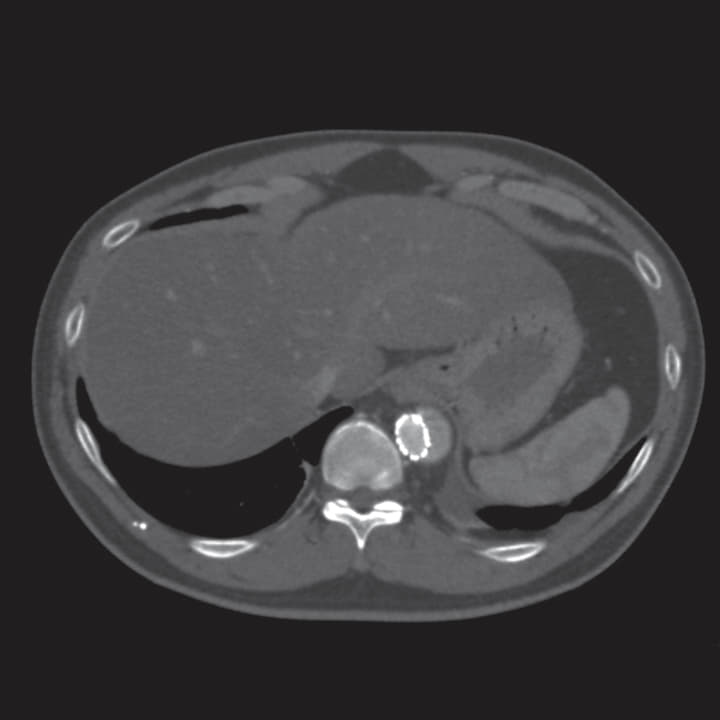

エントリーはT5レベルにあり大きさは29 mm、Zone 3大弯側の解離腔には比較的厚い(13 mm)偽腔内の血栓を認めたため、Zone 2ランディング+デブランチ(Ax-Axバイパス)の方針とした。

中枢は Zone 2の血管径32.0 mmに対して径34 mmのデバイスを選択し、末梢留置位置は下行大動脈が直線化しているTh12レベルへ、発症後1年以内であることからリモデリングを期待し、同部位真腔長径のおおよそ130%である26 mm デバイスを選択した(末梢31 mm/26 mm 10 cmテーパー、中枢34 mm/34 mm 20 cm積み上げ)。

術中術後に主要な有害事象は認めず、術後5日目に退院。術後CTでは遠位弓部偽腔の血栓化を認めた。また、術後6か月の単純CTでは胸部下行大動脈の著明なリモデリング(真腔拡大、偽腔縮小)を認めデバイスの末梢レベルではほぼ偽腔は消失した。